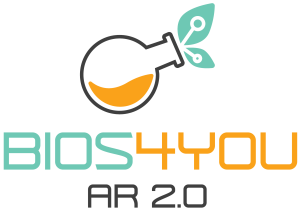

Um den vollen Nutzen aus dieser Lerneinheit über Photobiomodulation (PBM) zu ziehen, sollten Lernende ein grundlegendes Verständnis der menschlichen Biologie haben, einschließlich Zellen, Mitochondrien und Energiestoffwechsel. Vertrautheit mit den Eigenschaften von Licht, wie Wellenlänge und Intensität, hilft dabei zu verstehen, wie rotes und nahinfrarotes (NIR) Licht mit Geweben interagiert. Lernende sollten sich außerdem in digitalen Lernumgebungen und im Umgang mit interaktiven Werkzeugen wohlfühlen, da die Einheit Augmented-Reality-(AR)-Simulationen, Quizze und praktische Übungen beinhaltet. Kritisches Denken und Neugier werden gefördert, um Beobachtungen zu analysieren und über reale Anwendungen von PBM in Gesundheit, Sport und Alltag zu reflektieren. Vorkenntnisse in Phototherapie sind nicht erforderlich, aber ein Interesse daran, wie niedrig dosiertes Licht zelluläre Prozesse stimulieren und die Gewebeheilung unterstützen kann, wird das Lernerlebnis bereichern.